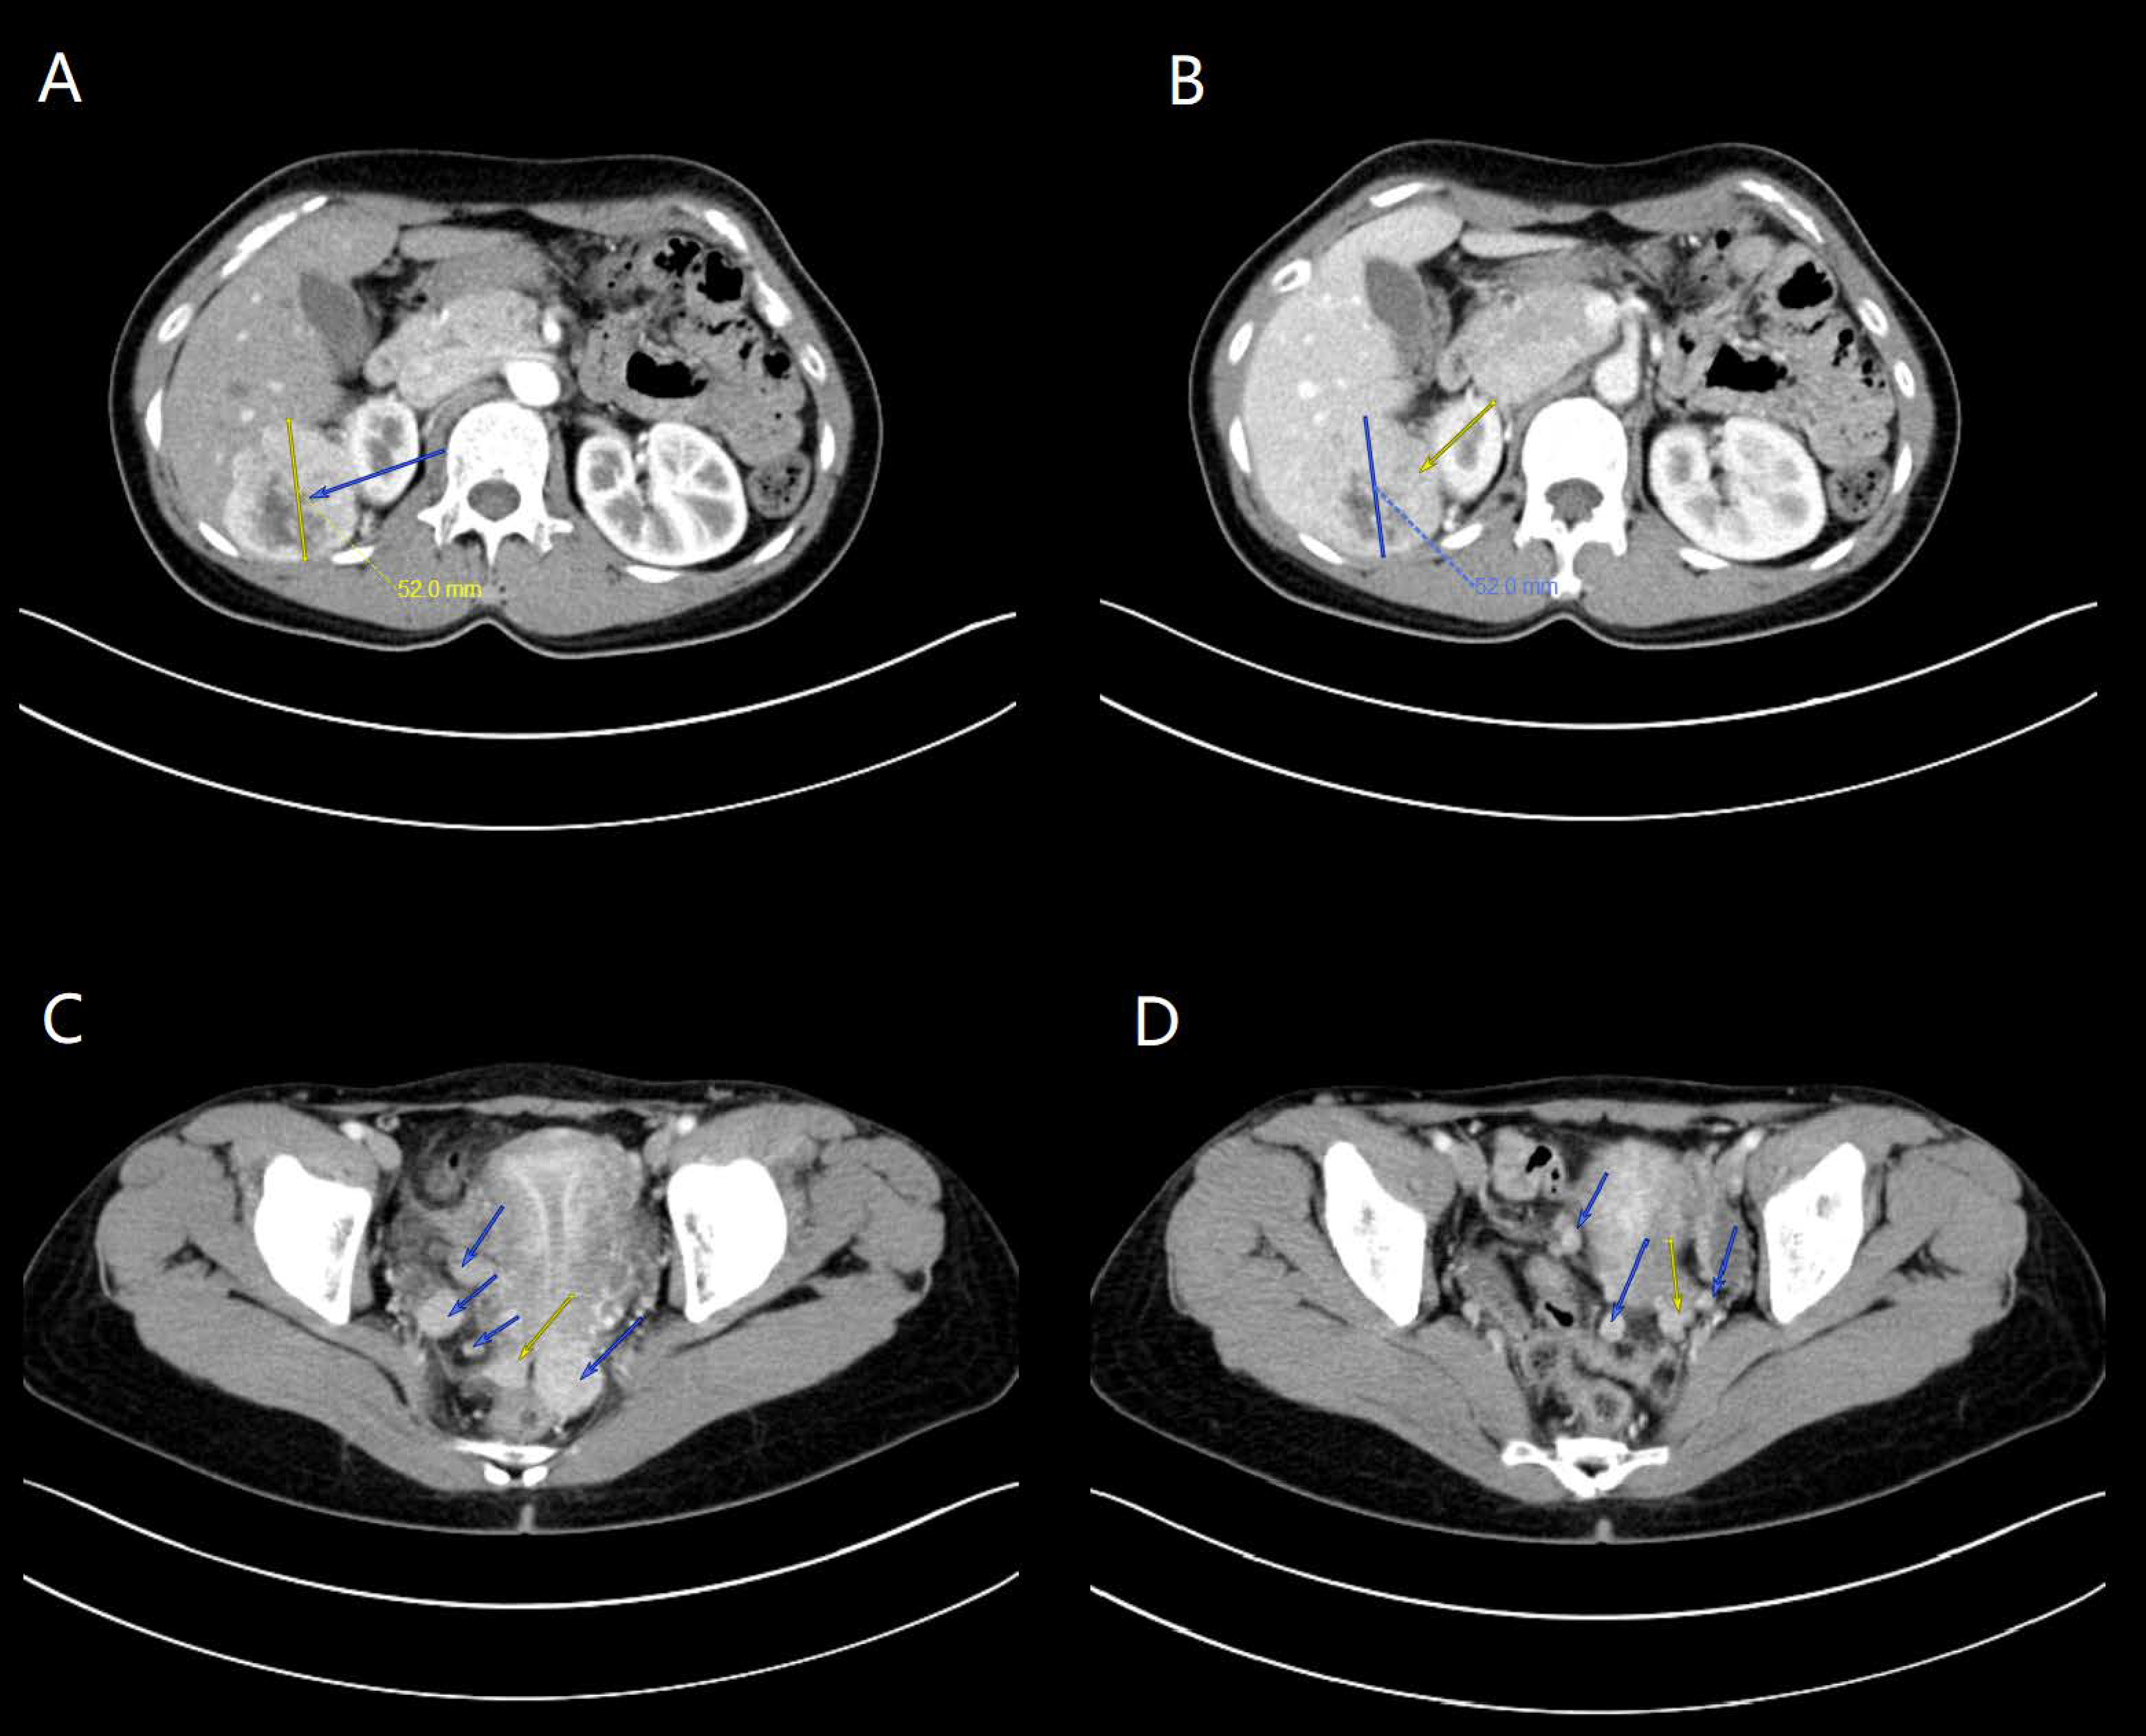

3.1.1. Case 1

3.1.2. Case 2